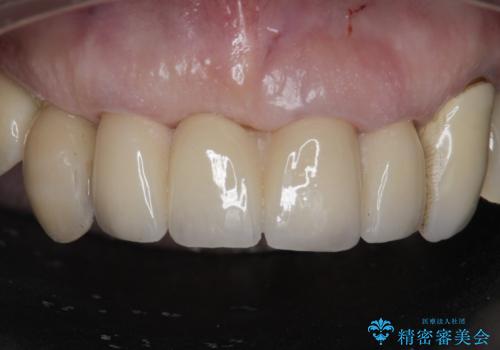

孫から口臭を指摘され来院、全顎治療で噛み合わせ、見た目、口臭全て劇的改善!